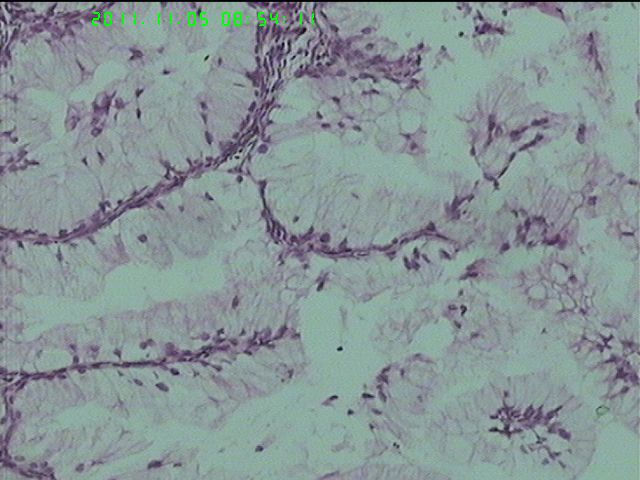

37岁女性患者,左卵巢肿块术中快速:恶性。术后左卵巢囊实性肿块14*9*5CM,灰黄色,部分乳头状,粘液样外观;子宫内膜厚1.5CM;网膜见多个小结节。图1--14左卵巢  15-19网膜  20--23宫腔

在图中有明确浸润吗?好像看不出来,但是网膜显示非侵袭性。宫腔图片没有显示浸润。请多上边缘处图像。

请临床查有无阑尾病变,排除阑尾肿瘤转移后,如果没有明确浸润,倾向粘液性*交界性肿瘤伴腹膜种植,肠型。

总之先排除阑尾来源,再看有无浸润,有浸润才打癌。